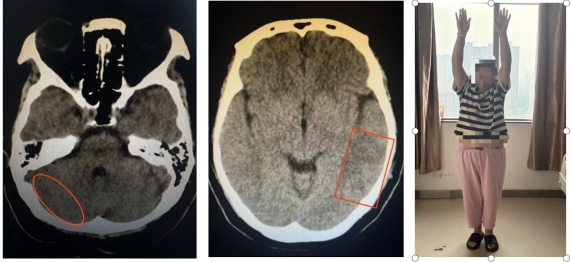

出院前复查CT及患者情况

血栓影消失 血肿吸收 患者完全康复